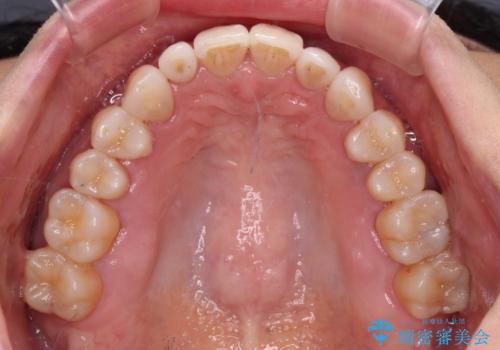

前歯のスペースが気になる インビザラインによる矯正治療

- 前歯の上下スペースによる食べにくさを気にして来院された患者様です。

インビザラインにより上下の前歯の隙間を閉じていくこととしました。

舌の突出癖があると上下前歯にスペースが開くため、矯正治療を機会に舌癖を改善するトレーニングを行ってもらい、矯正治療後の後戻りを防止するように指導しています。